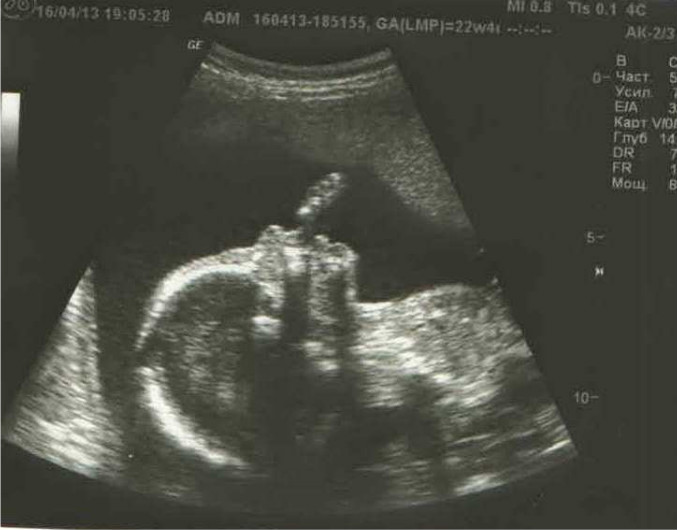

Сынишка :-*

У нас будет Мальчик!!! Ура-ура-ура!!! Мы очень-очень счастливы.

По порядку теперь. Вчера вечером ходили на УЗИ. Малыш наш развивается согласно сроку, всё у него на месте, всё в порядке. Узист сразу сказала, что будет мальчик. Правда мы само подтверждение не увидели - быстро малыш сменил всоё местоположение и стало не видно! Чудо наше расчудесное вовсю шевелил ручками, сосал пальчик, и ножками тарабанил. Папулечка счастлив безмерно, всем-всем сразу позвонили, сообщили радостную новость!!! Теперь нужно имя придумывать... Вот оно счастье!!!